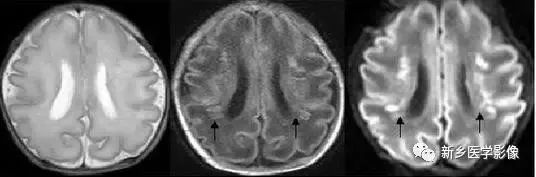

无脑回和巨脑回

无脑回和巨脑回是一组因神经元移行异常所致的脑回发育异常。巨脑回也称平滑脑。巨脑回指有部分脑回存在,这些脑回异常增大增宽、脑沟变浅。巨脑回主要位于额、颞部。无脑回主要位于顶、枕部。

临床上,无脑回和巨脑回畸形患儿均表现有小头畸形和轻微的面部异常,完全无脑回畸形常在两岁前死亡。不完全无脑回畸形通常能长期存活。

CT和MR均能够很好显示无脑回和巨脑回畸形,表现为大脑半球表面几乎呈光滑状,仅可见少数宽阔、粗大、平坦的脑回,脑沟缺如。脑灰质增厚、脑白质变薄,灰白质分界面异常平滑,见不到白质向灰质内伸入的现象。常见透明中隔腔存在,侧脑室扩大,蛛网膜下腔增宽。